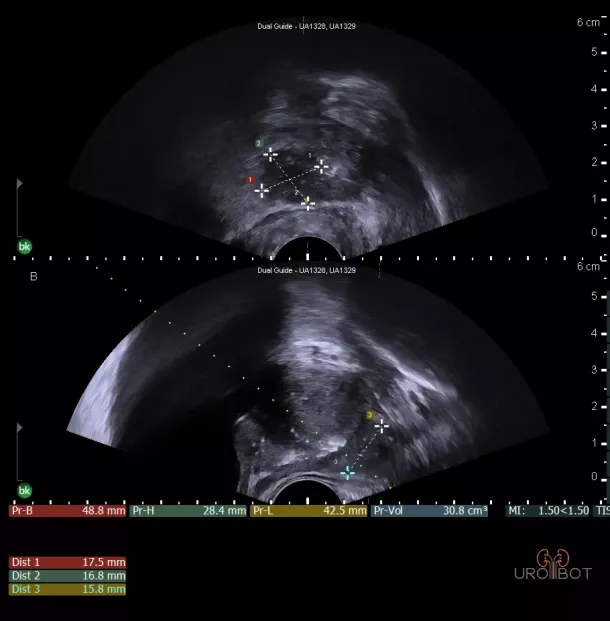

Prostata: Tumorbefund

Auf diesem Bild erkennt man die Prostata in zwei Ebenen mit Hilfe einer in den Enddarm eingeführten Ultraschallsonde.

Der ausgemessene Bereich, etwas dunkler dargestellt, entspricht einem größeren Tumorbefund in der Prostata.

Prostata: Tumorbefund

Auf diesem Bild erkennt man die Prostata in zwei Ebenen mit Hilfe einer in den Enddarm eingeführten Ultraschallsonde.

Der ausgemessene Bereich, etwas dunkler dargestellt, entspricht einem größeren Tumorbefund in der Prostata.